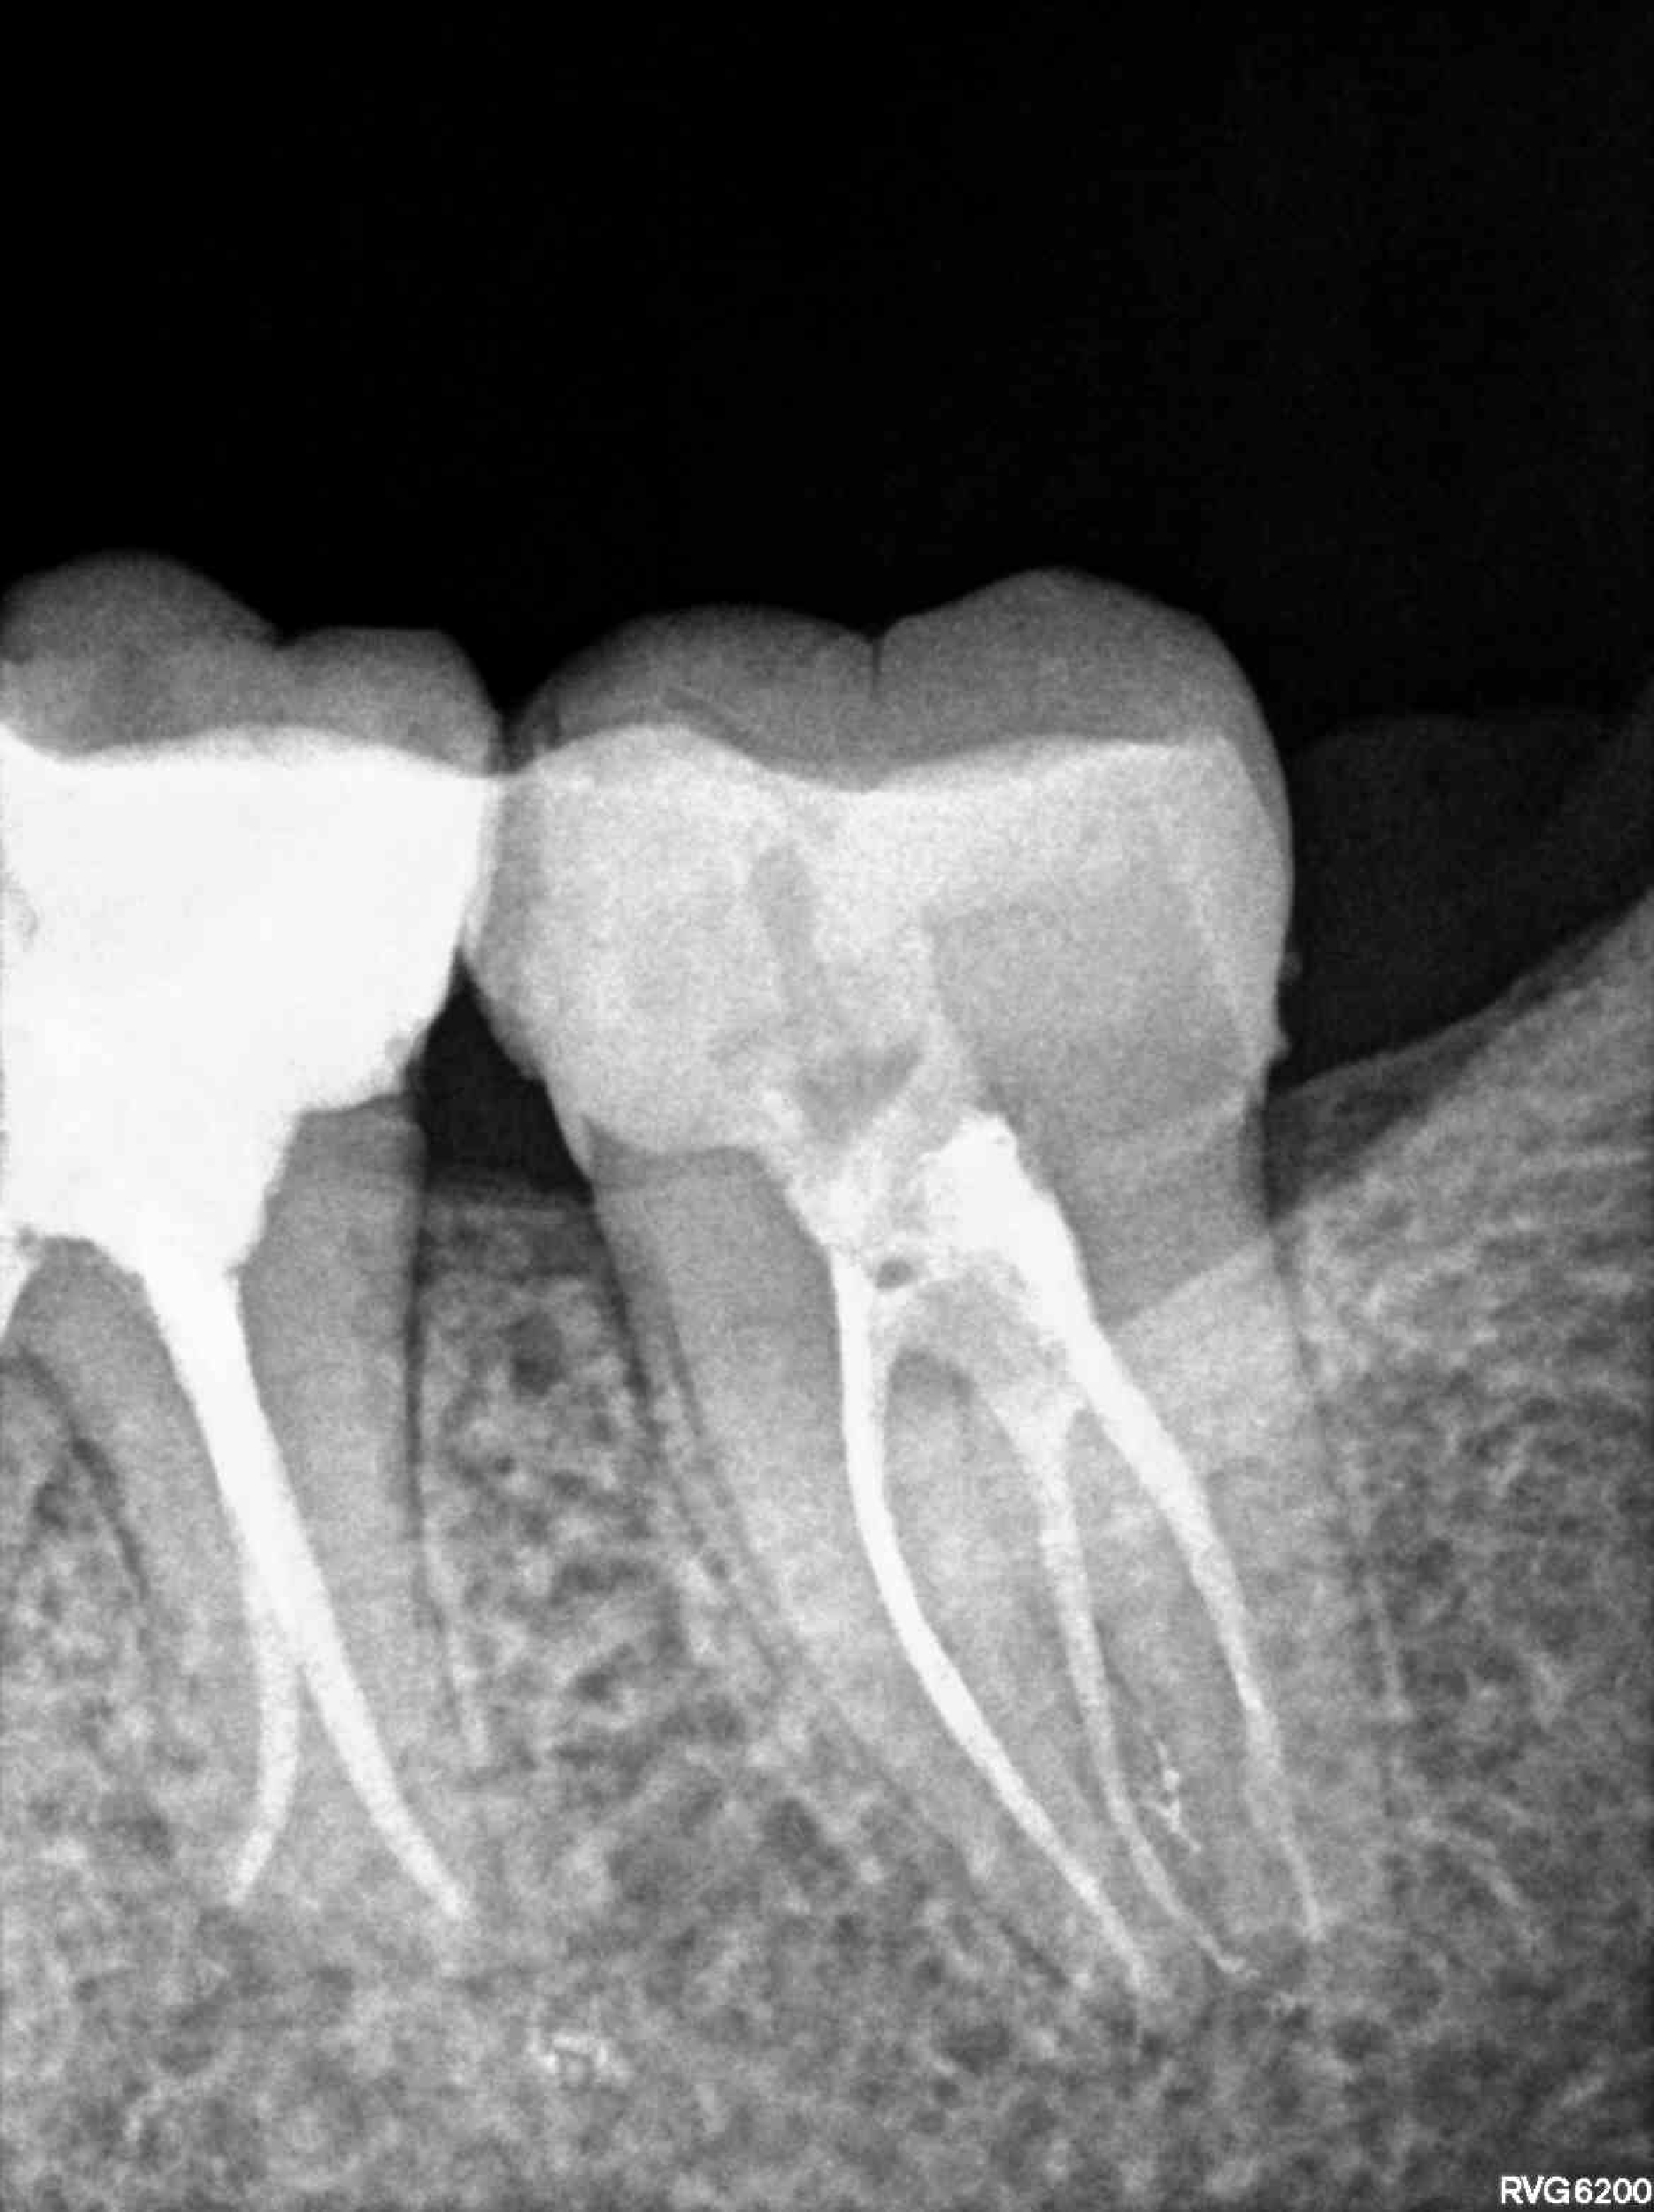

Categoría Endodoncia

Radiografías

Imágenes del tratamiento